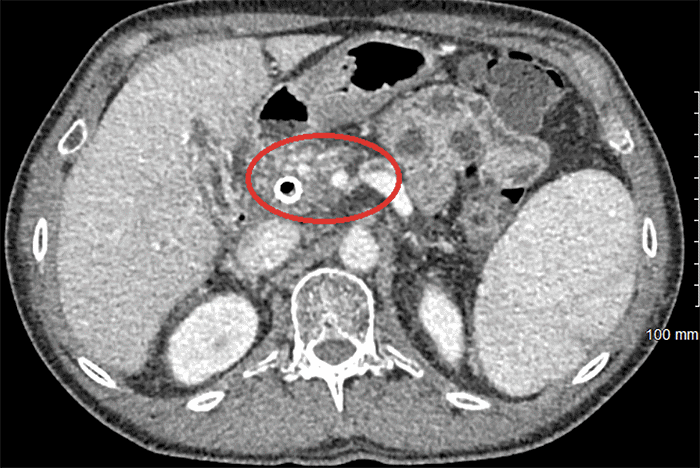

This procedure was complicated just over a week later by the development of sepsis secondary to an infected biloma that was successfully treated by percutaneous drainage and antibiotics. Liver function tests, particularly total and direct bilirubin, improved quickly after drainage. A follow-up CT was performed six weeks after the initial TIPS procedure and showed successful decompression of the pancreatic varices (Figure 3). He subsequently underwent successful pancreaticoduodenectomy with lateral PV resection. Final pathology revealed 1.3 cm moderately differentiated ductal carcinoma with negative margins and 24 negative lymph nodes. Surveillance duplex revealed a patent TIPS and left PV five months postop with no evidence of disease at six months postop.

Figure 3. CT Showing Decompression of Peripancreatic Varices 3 Weeks after TIPS. Published with Permission